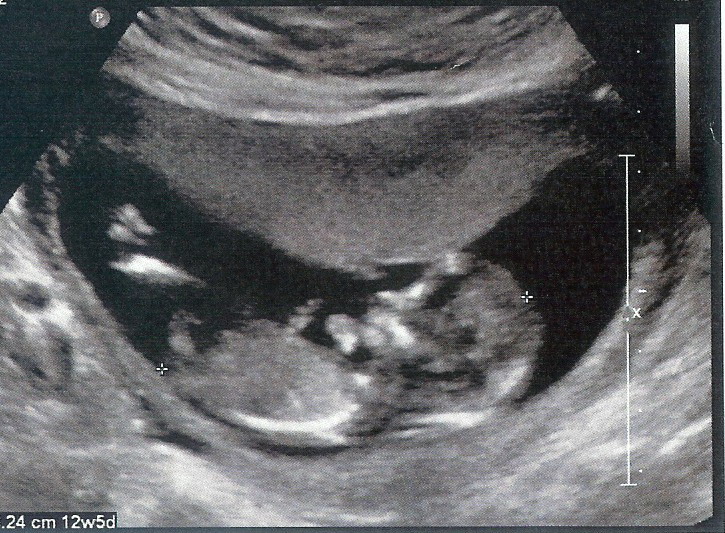

The following day we had my Nuchal Translucency scan. It’s a test that can only be done between 11 and 13 weeks where they measure the back of the baby’s neck to see if it’s thickened which is common in babies with Down Syndrome. They also do a blood test and these two tests together will tell you the risk factor for your baby. We just like to get an extra peek at the baby and 12 weeks is such a great time for an ultrasound because the little ones are moving like crazy even though you can’t feel it and they have tons of space to bounce around it.

I was 12 weeks 4 days at this scan (I was 12w1d at Adaline’s scan) and this baby was completely different from Adaline. Adaline moved like crazy…so much so that it took them the longest time to get her calm enough to measure her neck. She literally bounced off of the walls of my uterus and did flips and everything. This baby was very laid back. The movements were all small wiggles and hand movements, nothing big. It was so interesting to see how different this baby was compared to my daughter. Even though this baby stayed pretty still (s)he was still in the wrong position for the test and we had the opposite problem. The tech had me coughing and smacking my belly to try to get the baby to move into a different position and each time it would just fidget every so slightly as if to say, “Leave me alone! 5 more minutes, mom!”

Right after the scan they let me know that the neck looked normal but to remember that the blood test is important and then I went upstairs to have blood drawn. I’ve read online that many women get a finger prick for this test but both times I’ve had blood drawn from my arm. The hospital called a few days later to let me know that all of the test results looked normal and to give me the risk factor, which I don’t remember the exact number, but it was very low.